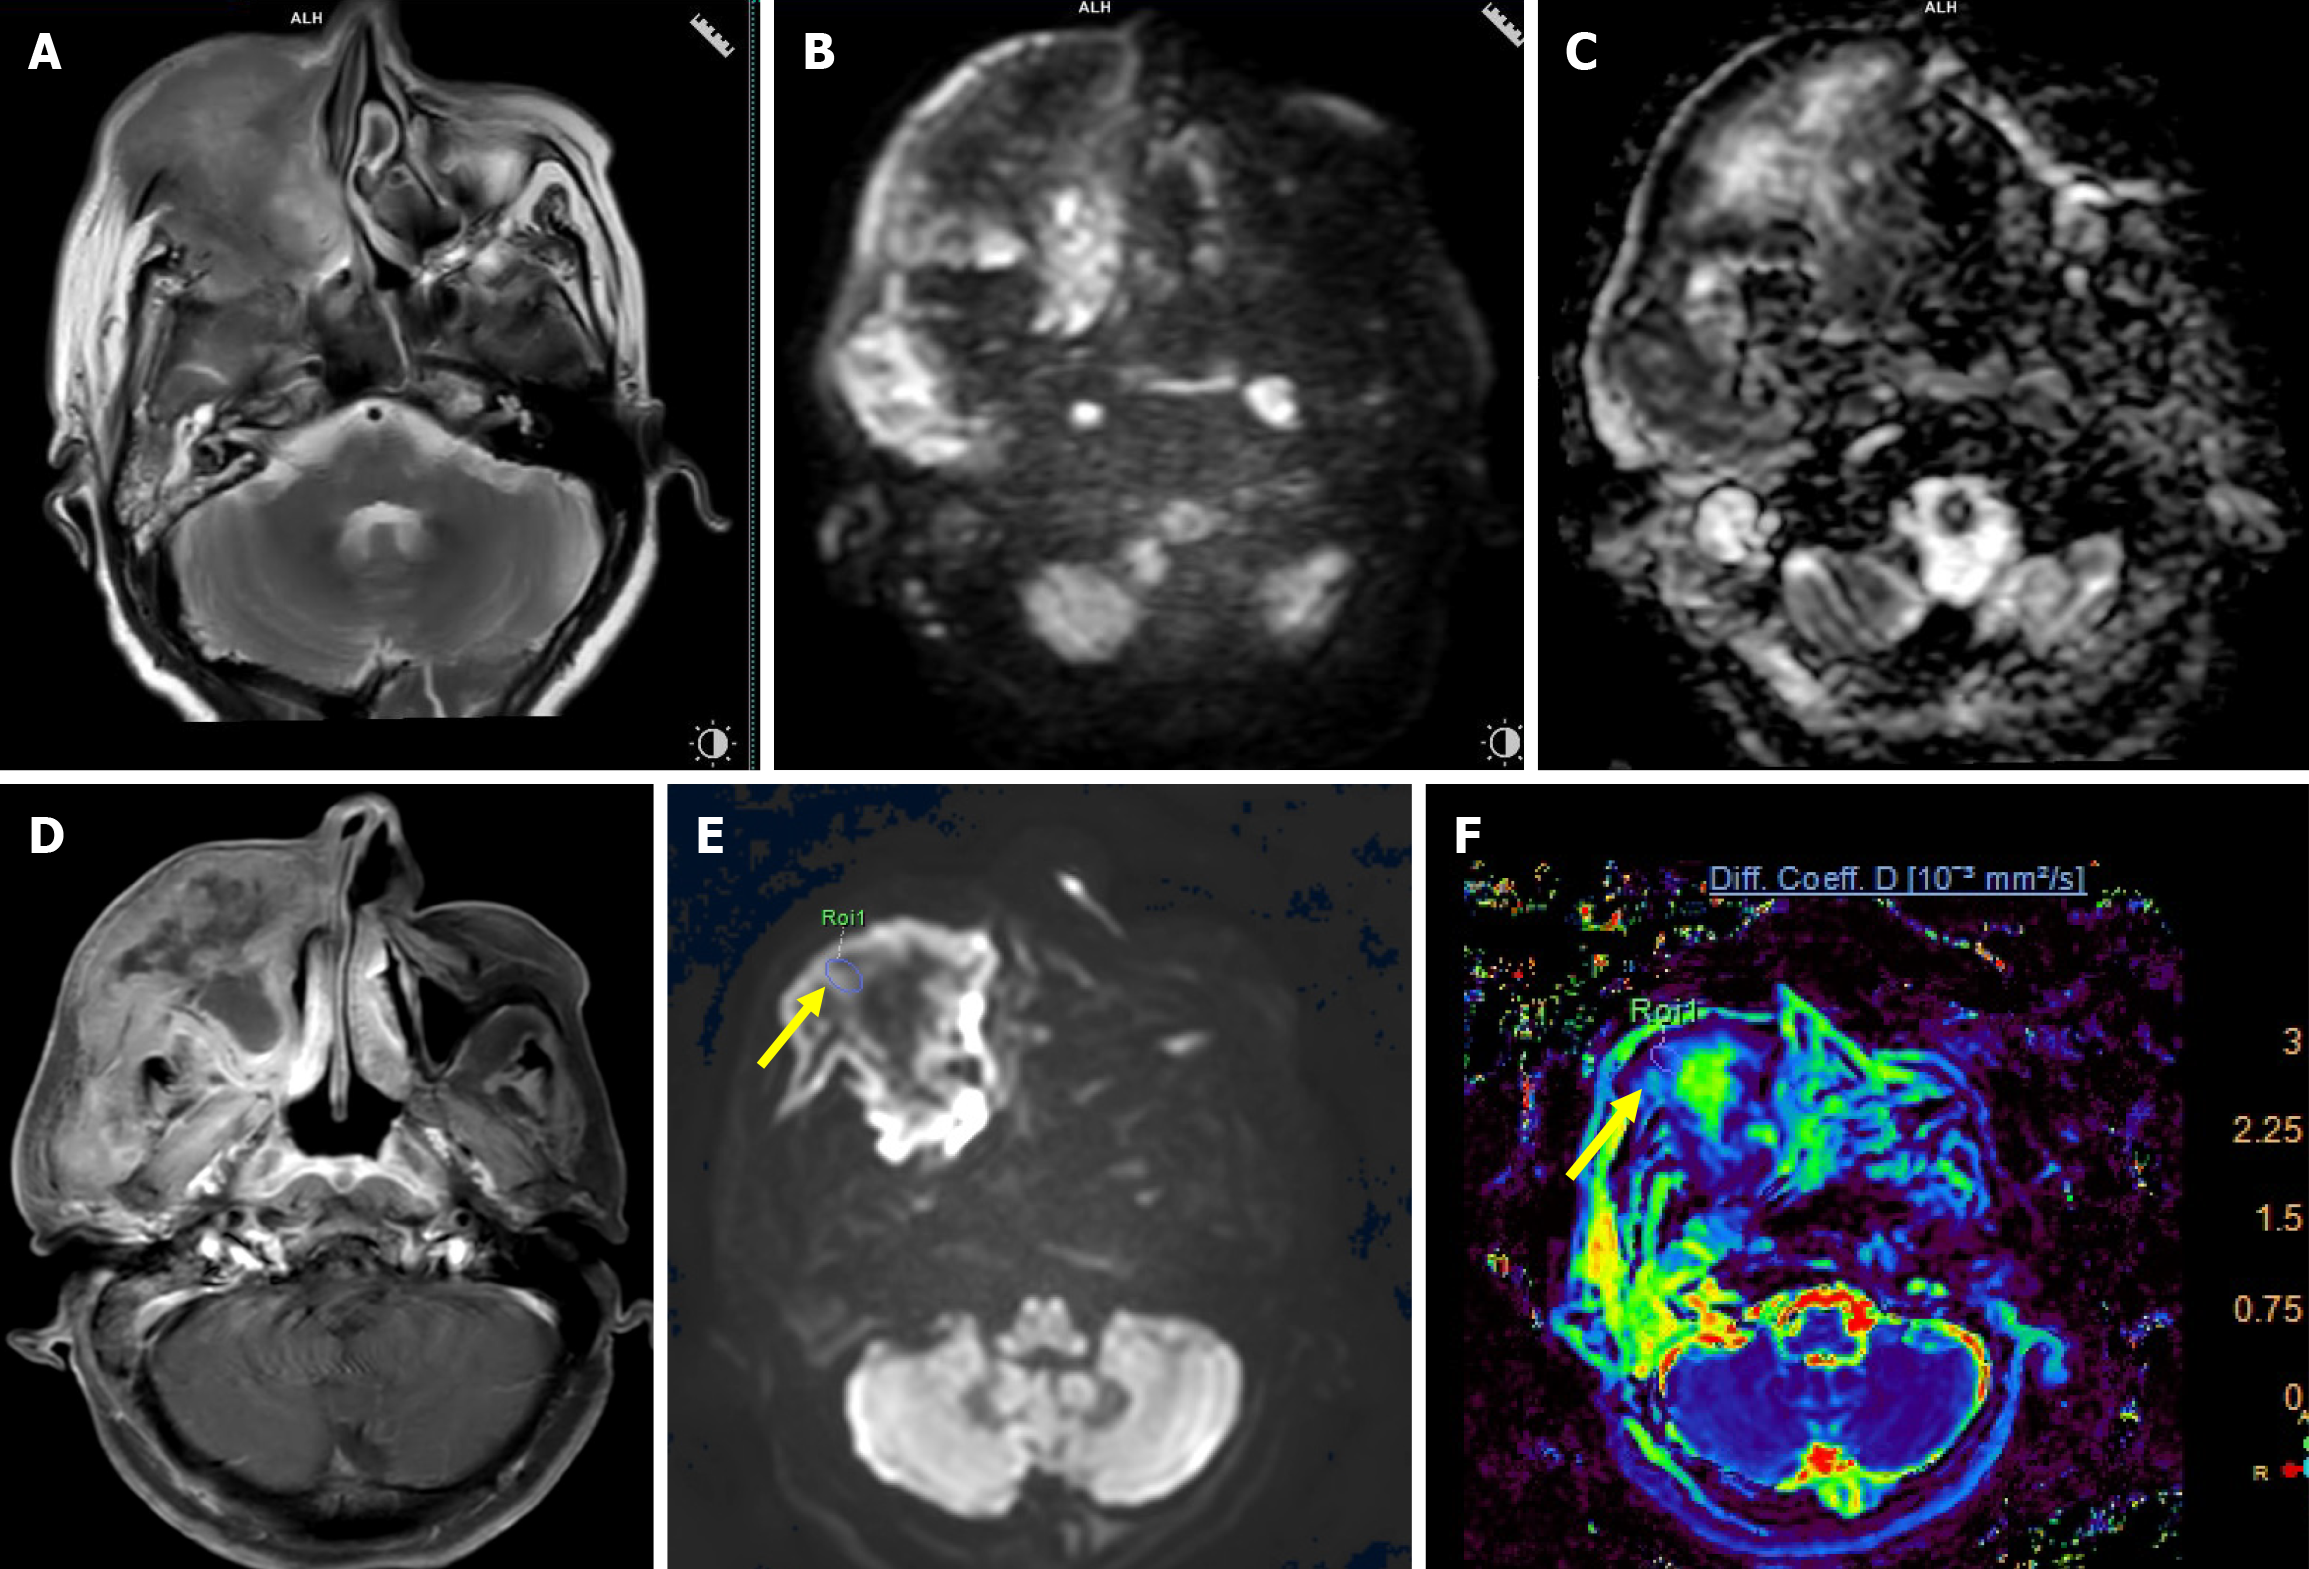

Figure 3 A 55-year-old female with undifferentiated carcinoma of the right maxillary sinus.

A: Axial T2-weighted image (T2WI) shows an ill-defined intermediate signal intensity mass epicentered in the right maxillary sinus with infiltration of the subcutaneous plane and skin; B: High b-value (b = 1000 seconds/mm2) image shows areas of high signal intensity; C: On corresponding apparent diffusion coefficient (ADC) map, similar areas showed hypointensity suggestive of true diffusion restriction (mean ADC value of 0.77 × 10-3 mm2/second); D: Axial post contrast T1WI image shows heterogeneous enhancement with central nonenhancing areas; E: High b-value image (b = 2000 seconds/mm2) of intravoxel incoherent motion imaging/diffusion kurtosis imaging sequence with region of interest (ROI) drawn (arrow) over the mass; F: True diffusion coefficient map after drawing ROI showed low value (0.68 × 10-3 mm2/second).